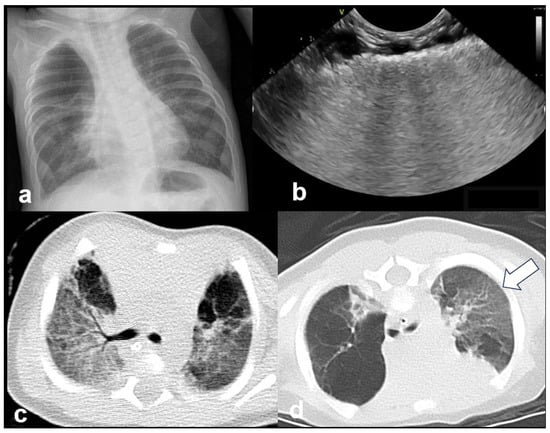

In RDS, lung ultrasound findings include consolidation or bilateral “white lung”, aero bronchograms, pleural line abnormalities, and the absence of A-lines (Figure 12, Figure 13, Figure 14 and Figure 15) [30,35,40,41].

Figure 12.

A frequent and characteristic imaging finding in RDS is the presence of B-Lines, bilaterally and throughout the lung parenchyma, in this case bilateral B-lines with no normal parenchyma (a) (absence of A-lines). Also, note the abnormal thickening ((a,b) arrows) of the pleural line (b). The overall sense is that of white lung.

Figure 13.

Normal to mild RDS: by chest X-ray (a); by LUS (b).

Figure 14.

Severe RDS shown on chest X-ray (a); LUS (b). The ability of the LUS to characterize the severity of the RDS is debatable.

Figure 15.

Severe RDS with sub-segmental(-pleural) consolidations. by LUS.

RDS is a common cause of neonatal respiratory failure, particularly in preterm infants, resulting from surfactant deficiency and alveolar collapse. LUS has become a valuable diagnostic tool for RDS, offering real-time visualization of lung pathology at the bedside [38,42,43,44,45]. A hallmark sonographic feature of RDS is the presence of dense, confluent B-lines throughout the lung fields, producing a “white lung” appearance due to the loss of normal aeration. Notably, the whole lung is typically involved, with a diffuse, bilateral distribution that distinguishes RDS from more localized pulmonary conditions [37,46,47]. Additionally, interspersed consolidations may be present, including hypoechoic and subpleural areas of alveolar collapse, reflecting regions of complete de-aeration. These consolidations often lack air bronchograms and are associated with irregular or thickened pleural lines. The combination of diffuse B-line patterns, global lung involvement, and patchy consolidations provides a highly suggestive ultrasound profile of RDS and facilitates early diagnosis. In addition, for RDS, LUS may be used for severity assessment and the monitoring of treatment response in the neonatal intensive care setting [16,20,27,29]. The ability of the LUS to characterize the severity of the RDS is debatable (Figure 14 and Figure 16) [48].

Figure 16.

Interstitial emphysema shown on chest x-ray (a) and LUS (b). This case underlines the superiority of CXR in differentiating this pathology from RDS, which has a similar LUS appearance.